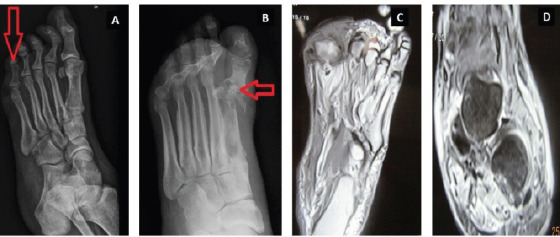

Materials and methods: This prospective study was carried out in 50 patients. Diagnosis of OM was made by clinical examination and confirmed by radiological studies. The serum levels of ESR, CRP, and PCT were determined on admission in all the patients and then on day 15 and day 30 in the osteomyelitic group.